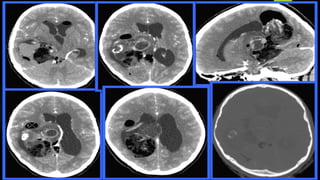

NCCT

T1WI

T1 + C T2WI